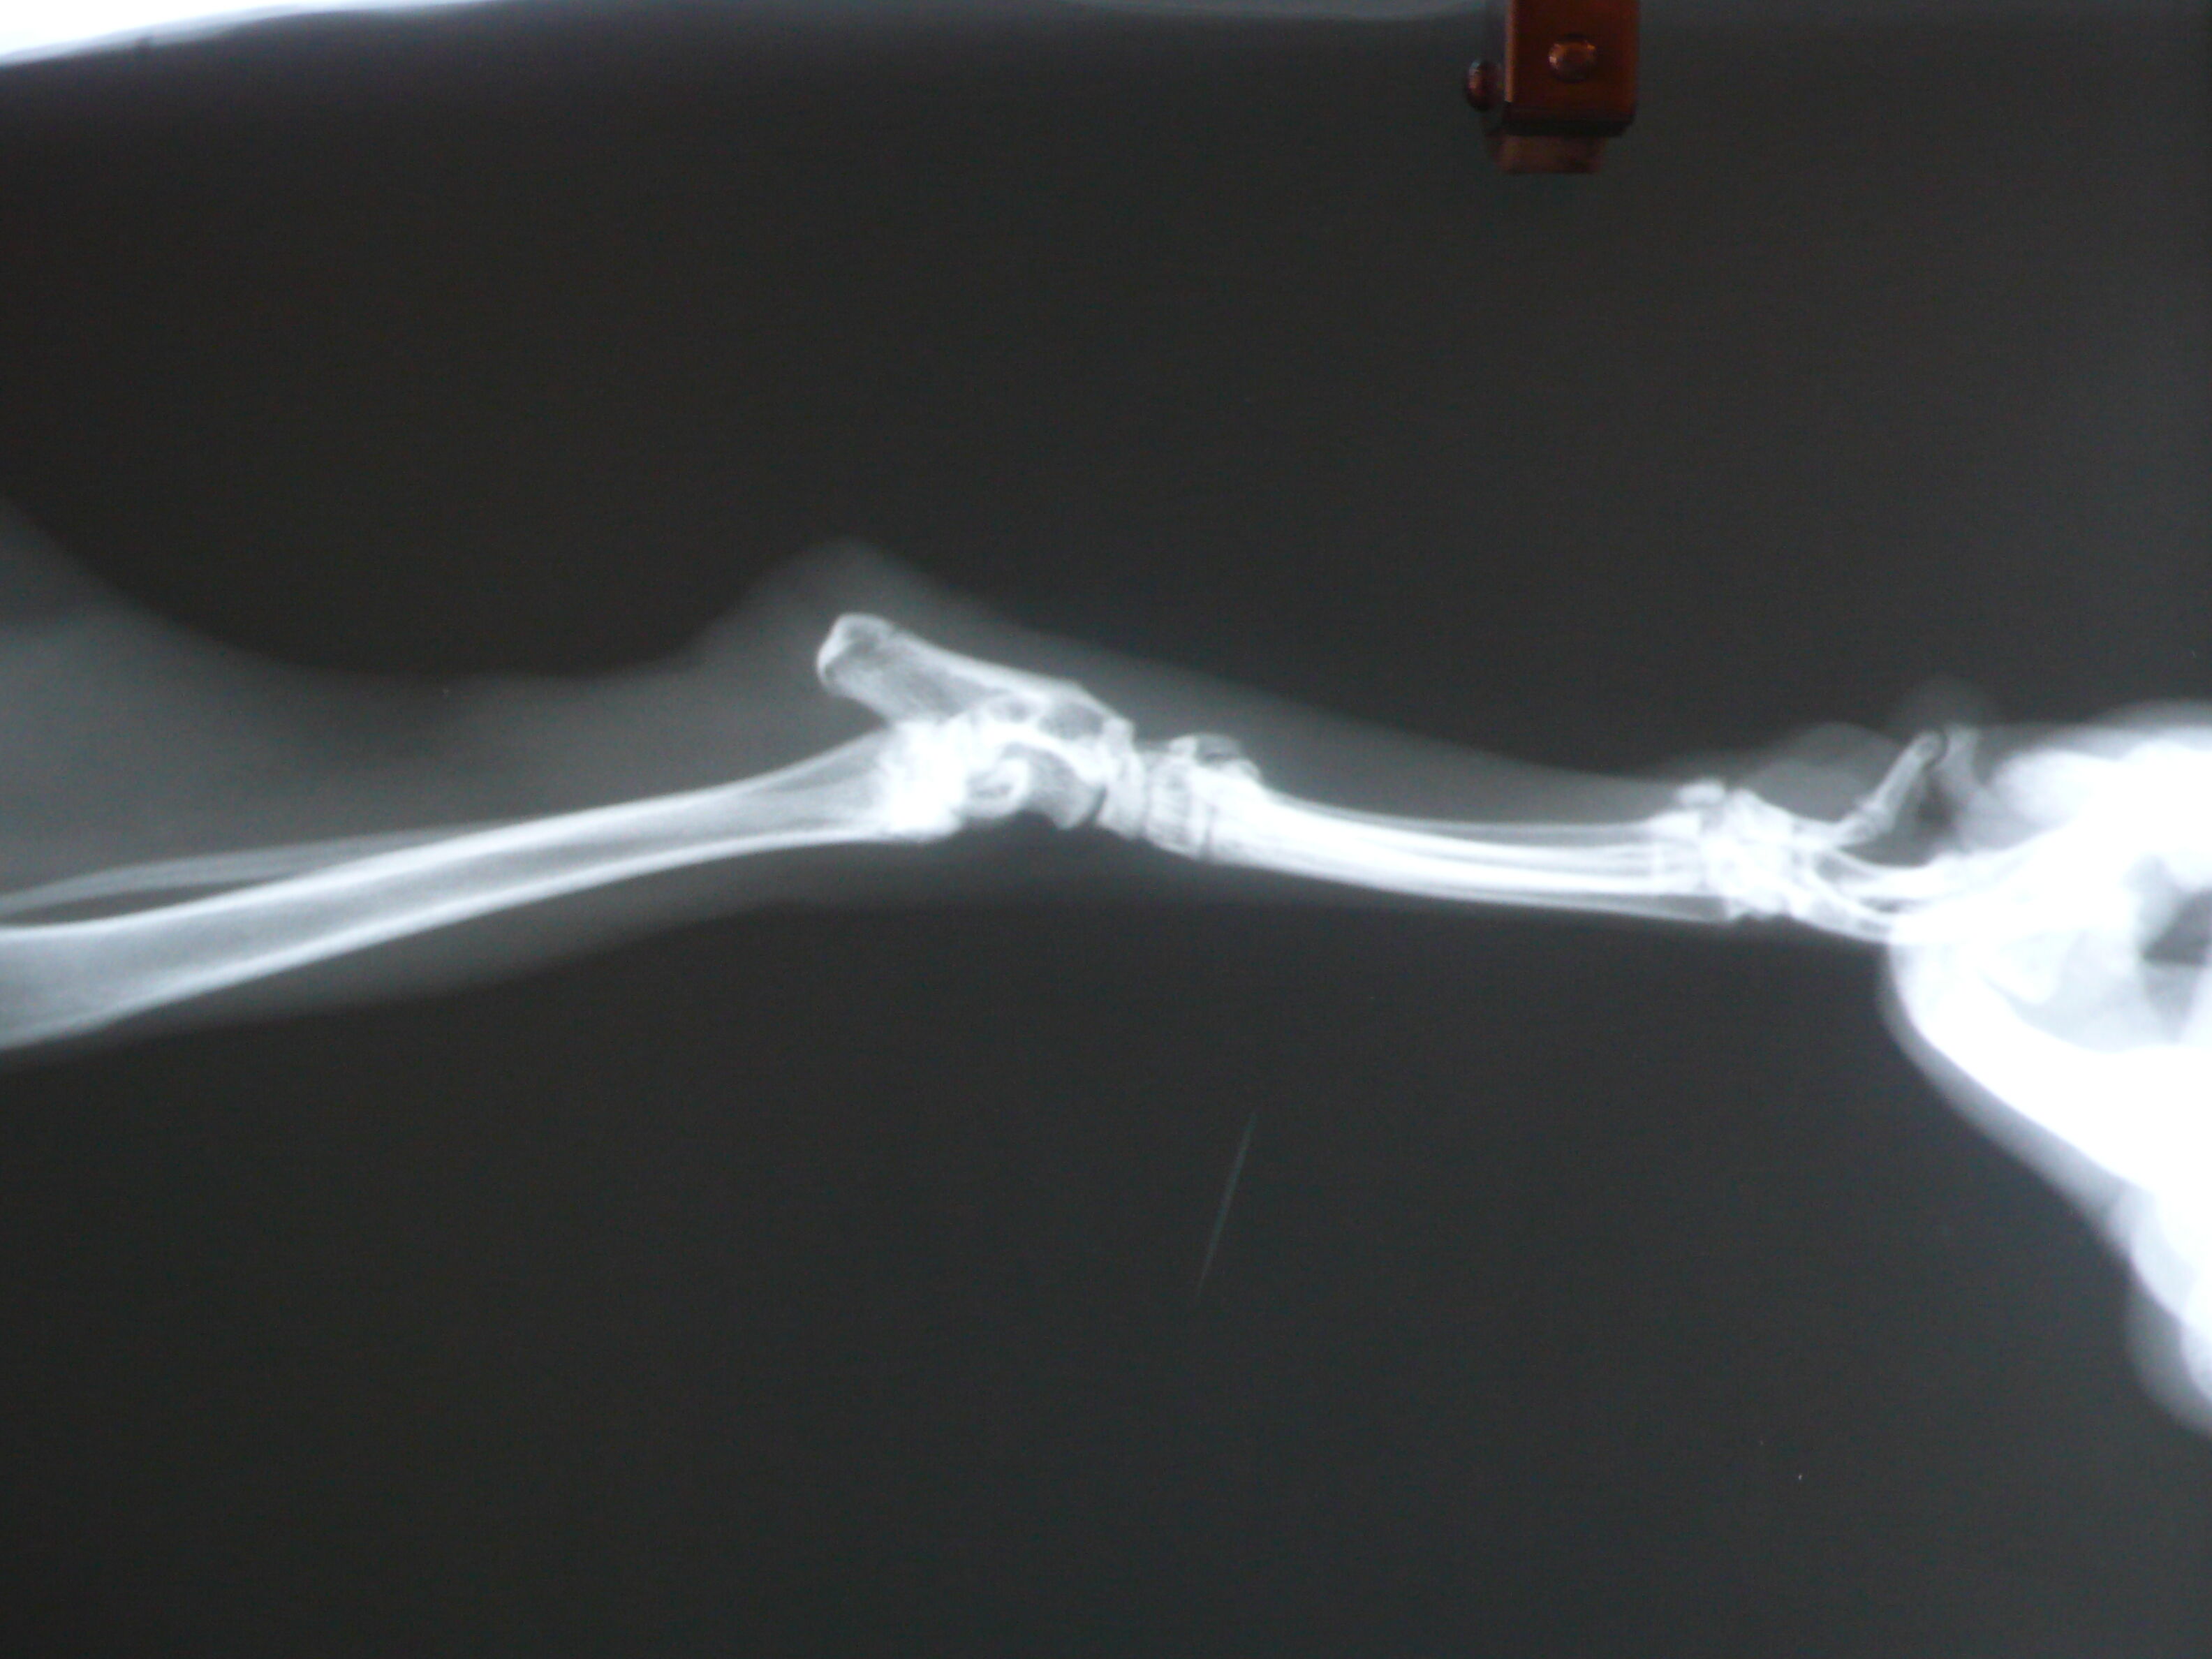

檢查後發現在右後腳的腳踝上方有一長條不明切割傷,以致腳踝處有水腫發炎現象,也因長時間拖行導致腳底磨傷無法癒合,之後,又在腳踝割傷處觸診到一個腫塊經開刀後發現肌肉內包覆了一條鐵絲,上方血管已發黑捲曲佈滿黑色鐵屑,同時,也確定小公橘的靭帶已被切斷只能靠其他肌肉支撐。